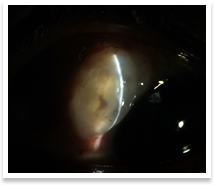

Glaucoma refers to progressive damage of the optic nerve(the nerve that carries visual information to the brain) secondary to numerous causes, the most well known of which are raised intraocular pressure(IOP, the pressure inside the eye) and vascular(blood supply related) disturbances. The essential feature of this condition is excavation of Optic Disc(the white portion of the disc) along with loss of the neuroretinal rim(the pink portion of the disc) Glaucoma affects the peripheral vision first (our perception of things in and around our point of interest or fixation point when we look at something) and the central vision later. Hence, it might be very difficult to pick up glaucoma until the damage is advanced. There are two major types of glaucoma : |